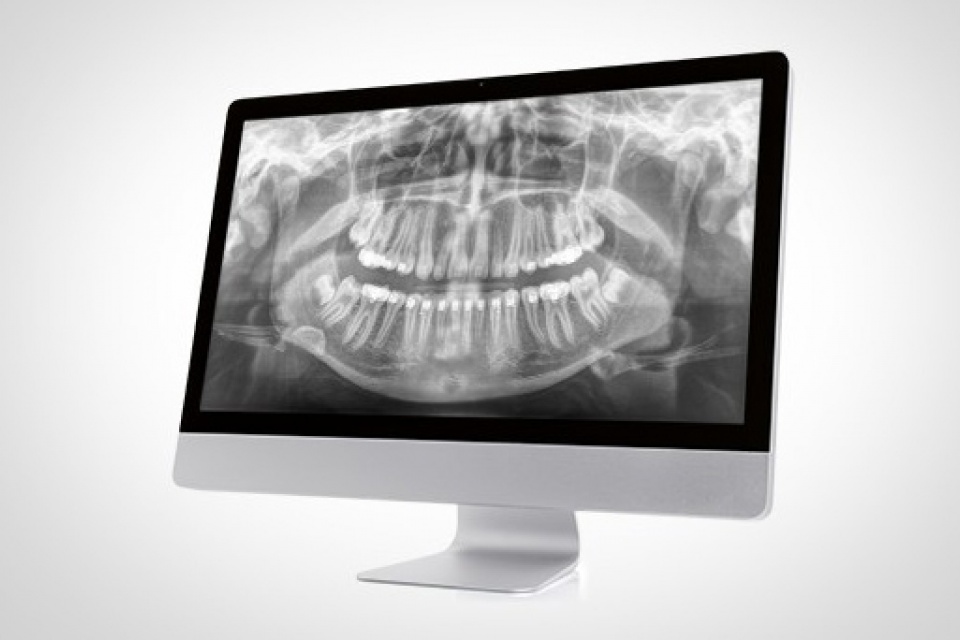

OPG neboli Ortopantomogram je přehledný panoramatický rentgenový snímek zachycující dentici, obě čelisti, čelistní klouby, část nosní dutiny a část čelistní dutiny vyšetřovaného.

Zhotovujeme intraorální „malé“ rentgenové snímky, důležité pro detekci kazů, kvality výplní jak korunkových tak kořenových, stavu parodontu, množství zubního kamene aj.